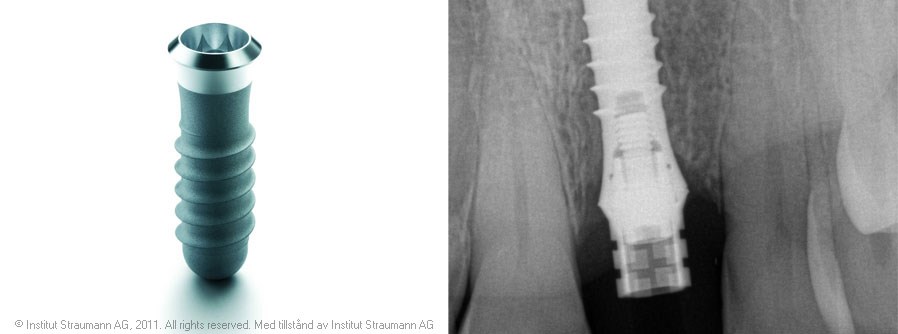

Implantat

Vid enstaka eller mer omfattande tandförluster kan man med implantat på ett skonsamt sätt återskapa estetik och funktion. Vi arbetar sedan 1994 med implantat från Straumann ITI som vi har en mycket god erfarenhet av. En stor fördel med detta system är att det bara behövs en operation.

Lyckandefrekvensen är dessutom mycket hög. Tänderna på implantaten upplevs och fungerar som ”egna” tänder. All behandling utförs på kliniken vilket är praktiskt och tryggt för dig som patient.